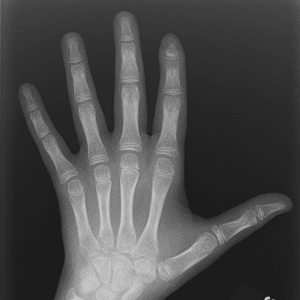

Pediatric Radiographs